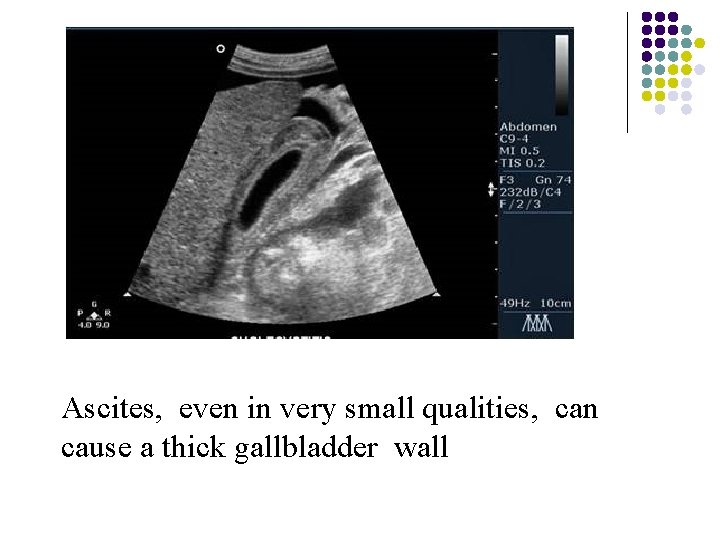

Ascites, even in very small qualities, can cause a thick gallbladder wall

Ascites